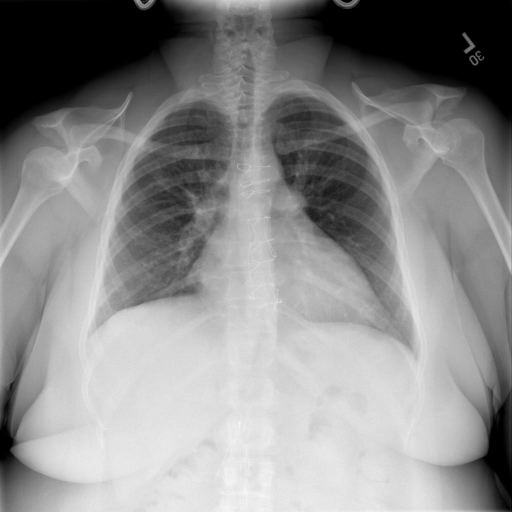

# 本文贡献 ![](./assets/images/xrayglm.png) - 借助ChatGPT以及公开的数据集,我们构造了一个`X光影像-诊断报告`对的医学多模态数据集; # 数据集 - [MIMIC-CXR](https://physionet.org/content/mimic-cxr-jpg/2.0.0/)是一个公开可用的胸部X光片数据集,包括377,110张图像和227,827个相关报告。 - [OpenI](https://openi.nlm.nih.gov/faq#collection)是一个来自印第安纳大学医院的胸部X光片数据集,包括6,459张图像和3,955个报告。 在上述工作中,报告信息都为非结构化的,不利于科学研究。为了生成合理的医学报告,我们对两个数据集进行了预处理,并最终得到了可以用于训练的**英文报告**。除此之外,为了更好的支持中文社区发展,借助ChatGPT的能力,我们将英文报告进行了中文翻译,并最终形成了可用于训练的数据集。 |数据集|数量|下载链接| |:-|:-|:-| |MIMIC-CXR-zh|-|-| |OpenI-zh|6,423|[诊疗报告](./data/Xray/openi-zh.json) 、[X光影像](https://pan.baidu.com/s/13GBsDMKf6xBZBSHpoWH_EA?pwd=k9sh)| # 快速上手 1. 安装环境 ```bash # 安装依赖 pip install -r requirements.txt # 国内换源安装依赖 pip install -i https://mirrors.aliyun.com/pypi/simple/ -r requirements.txt ``` 此时默认会安装`deepspeed`库(支持`sat`库训练),此库对于模型推理并非必要,同时部分`Windows`环境安装此库时会遇到问题。 如果想绕过`deepspeed`安装,我们可以将命令改为: ```bash # 安装依赖 pip install -i https://mirrors.aliyun.com/pypi/simple/ -r requirements_wo_ds.txt # 安装SwissArmyTransformer pip install -i https://mirrors.aliyun.com/pypi/simple/ --no-deps "SwissArmyTransformer>=0.3.6" ``` 2. 模型推理 CLI推理: ```python python cli_demo.py --from_pretrained checkpoints/finetune-XrayGLM-05-25-01-04 --prompt_zh '详细描述这张胸部X光片的诊断结果' ``` 更多[参数](https://github.com/WangRongsheng/XrayGLM/blob/main/cli_demo.py#L16) # 效果展示 诊断: |X光影像|诊疗报告(医生)|XrayGLM| |:-|:-|:-| |![](./data/Xray/2_1.png)|根据X射线图像,心脏大小正常,肺部看起来很清晰。已经排除了肺炎、积液、水肿、气胸、腺病、结节或肿块的存在。该发现表明一切正常。换句话说,总体印象是胸部正常。|X光片显示,心脏大小正常。肺部没有气胸或胸腔积液的证据。骨骼结构看起来没有任何异常。总的来说,X光片表明没有发现急性心肺疾病的迹象。| |![](./data/Xray/2882_1.png)|X光图片显示没有扭曲的区域、可疑的骨质不透明度或胸腺积液。心脏大小轻微增大,但非常稳定。此外,没有气胸的证据,肺野也正常。总体来说,X光片显示没有急性心脏异常,但要注意轻微的心脏扩大。|X光片显示,心脏大小正常。肺部和纵隔轮廓清晰,没有气胸或胸腔积液的证据。骨骼结构完整,没有任何急性异常。| |![](./data/Xray/2577_1.png)|心影形态在正常范围内。没有急性骨质异常。有可能出现没有明显的吸水或肺实质状况的线索。没有大面积积液或气胸。有可能怀疑其有误吸或肺实质问题。为了确诊和治疗,可能需要进行适当的影像学随访。|心脏大小正常,肺部和纵隔轮廓清晰。没有急性异常或活动受限的证据。没有任何明显的气胸、胸腔积液或肺不张的迹象。此外,也没有发现任何局灶性骨质异常或其他急性疾病。| 多轮对话: |X光影像|诊疗报告(医生)| |:-|:-| |![](./data/Xray/861_1.png)|右侧主动脉突出观察到。心脏大小正常。胸部未发现明显的肺气肿、胸膜积液或可疑的肺部病变。报告指出已知右侧主动脉情况正常。| ```bash >> X光影像路径:./data/Xray/861_1.png >> 用户:这是一张什么图? >> XrayGLM:这张图片显示的是一张肺部检查的X光片。 >> 用户:请描述这张胸部X光片的诊断结果 >> XrayGLM:心脏大小正常,肺部清晰。没有急性心肺疾病的证据。 >> 用户:是否存在肺气肿? >> XrayGLM:没有肺气肿。心脏大小正常,肺部清晰。没有发现急性心肺疾病的证据。 >> 用户:平时饮食该注意什么? >> XrayGLM:饮食应该健康,均衡。建议增加蛋白质的摄入量,因为蛋白质有助于维持肌肉和骨骼的健康。多食用蔬菜、水果、全谷物以及健康的脂肪来源如橄榄油、鱼类等可以帮助获得足够的维生素和矿物质。此外,避免过度饮酒或吸烟,这些习惯可能会对心脏健康产生负面影响。 ``` # 项目致谢 1. [VisualGLM-6B](https://github.com/THUDM/VisualGLM-6B)为我们提供了基础的代码参考和实现; 2. [MiniGPT-4](https://github.com/Vision-CAIR/MiniGPT-4)为我们这个项目提供了研发思路; 3. ChatGPT生成了高质量的中文版X光检查报告以支持XrayGLM训练; 4. [gpt_academic](https://github.com/binary-husky/gpt_academic)为文档翻译提供了多线程加速; 5. [MedCLIP](https://github.com/RyanWangZf/MedCLIP) 、[BLIP2](https://huggingface.co/docs/transformers/main/model_doc/blip-2) 、[XrayGPT](https://github.com/mbzuai-oryx/XrayGPT) 等工作也有重大的参考意义; ![](./assets/images/mpu.png) 这项工作由[澳门理工大学应用科学学院](https://www.mpu.edu.mo/esca/zh/index.php)硕士生[王荣胜](https://github.com/WangRongsheng) 、[段耀菲](https://github.com/IsBaSO4) 、[李俊蓉](https://github.com/lijunrong0815)完成,同时这项工作受到[檀韬](https://scholar.google.com/citations?hl=zh-CN&user=lLg3WRkAAAAJ)副教授、[彭祥佑](http://www.patrickpang.net/)老师的帮助支持。 *特别鸣谢:[USTC-PhD Yongle Luo](https://github.com/kaixindelele) 提供了有3000美金的OpenAI账号,帮助我们完成大量的X光报告翻译工作 # 免责声明 本项目相关资源仅供学术研究之用,严禁用于商业用途。使用涉及第三方代码的部分时,请严格遵循相应的开源协议。模型生成的内容受模型计算、随机性和量化精度损失等因素影响,本项目无法对其准确性作出保证。即使本项目模型输出符合医学事实,也不能被用作实际医学诊断的依据。对于模型输出的任何内容,本项目不承担任何法律责任,亦不对因使用相关资源和输出结果而可能产生的任何损失承担责任。 # 项目引用 如果你使用了本项目的模型,数据或者代码,请声明引用: ```bash @misc{wang2023XrayGLM, title={XrayGLM: The first Chinese Medical Multimodal Model that Chest Radiographs Summarization}, author={Rongsheng Wang, Yaofei Duan, Junrong Li, Patrick Pang and Tao Tan}, year={2023}, publisher = {GitHub}, journal = {GitHub repository}, howpublished = {\url{https://github.com/WangRongsheng/XrayGLM}}, } ``` # 使用许可 此存储库遵循[CC BY-NC-SA](https://creativecommons.org/licenses/by-nc-sa/4.0/) ,请参阅许可条款。